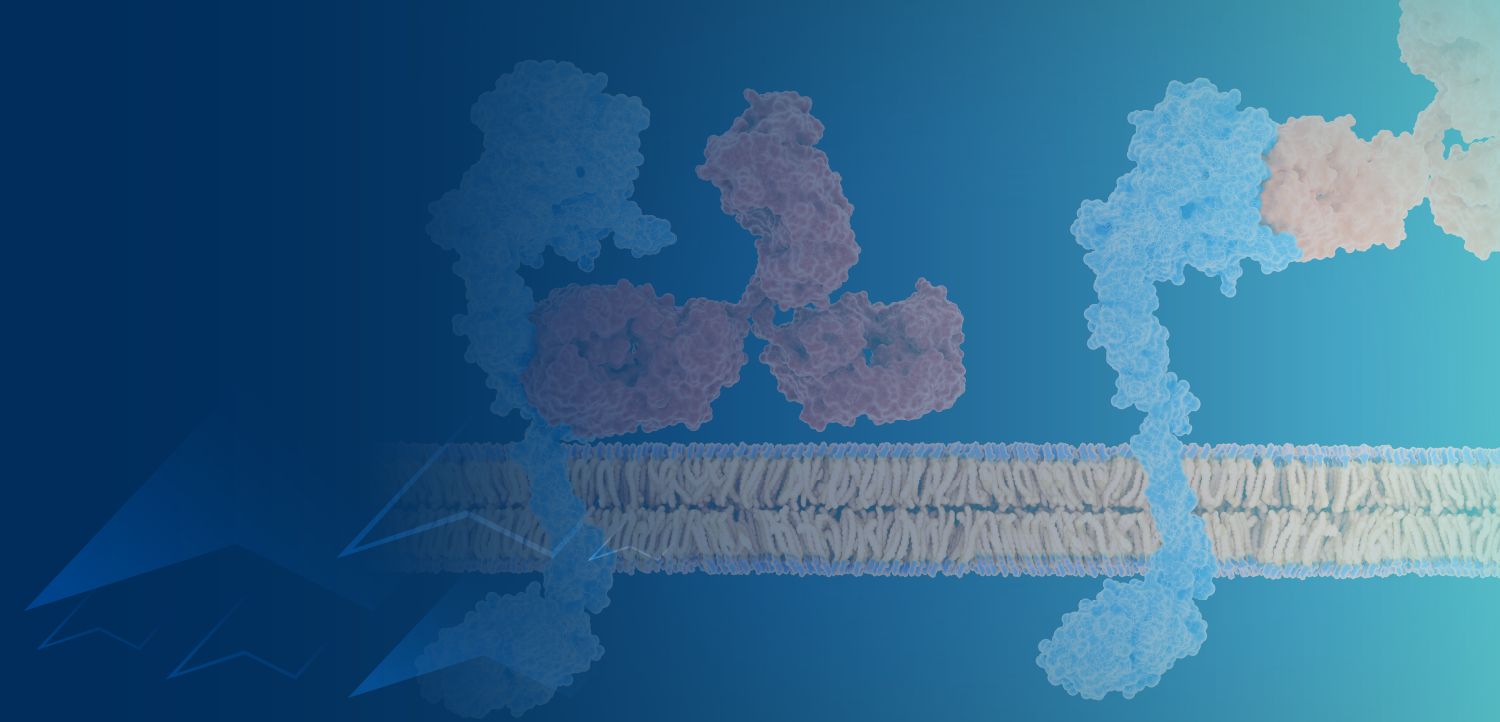

Rachel N. Grisham, MD, discusses the mechanism of action of VS-6766 in patients with recurrent low-grade serous ovarian cancer.

Robert Wenham, MD, MS, FACOG, FACS, discusses the basis for combining chemotherapy, PARP inhibitors, and VEGF inhibitors with immunotherapy in ovarian cancer and ongoing research with ADCs in the field.

Robert Wenham, MD, MS, FACOG, FACS, discusses novel immunotherapy combinations for the treatment of patients with ovarian cancer.

February 10, 2021 - A biologics license application has been submitted to the FDA for the accelerated approval of the antibody-drug conjugate tisotumab vedotin for use in patients with recurrent or metastatic cervical cancer that has progressed on or following chemotherapy.